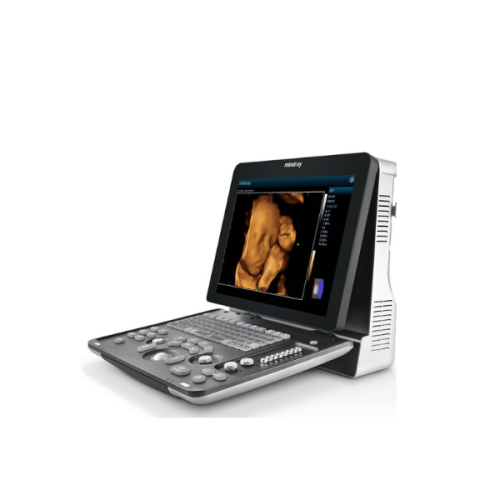

Description

GE Vivid 7 Imaging Modes

GE Vivid 7 Features: